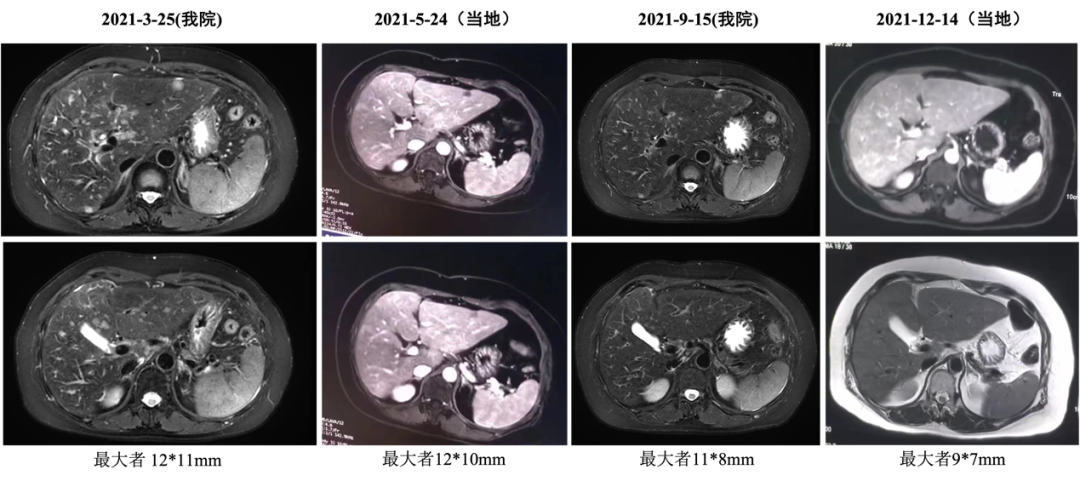

▌六线治疗:

2020-12-22始行吉西他滨+曲妥珠单抗(汉曲优)+帕妥珠单抗治疗,具体:吉西他滨1g/m2 1.6g d1、1.8g d8;曲妥珠单抗首次 8mg/kg 520mg,以后6mg/kg 390mg,帕妥珠单抗首次840mg,以后420mg,d1,Q21d;自第10周期开始双靶维持治疗。2021-03-25复查:肝内多发转移较前减少、缩小(较大24x20mm→12x11mm),肝门区及门腔间隙淋巴结缩小(28*18mm→12*7mm),左侧肋骨转移减轻),最佳评效PR。2021-12-15头MRI示可疑脑膜转移,评效PD,PFS为12月。不良反应:手足麻木2度,肝功损伤2度。

图7 六线治疗